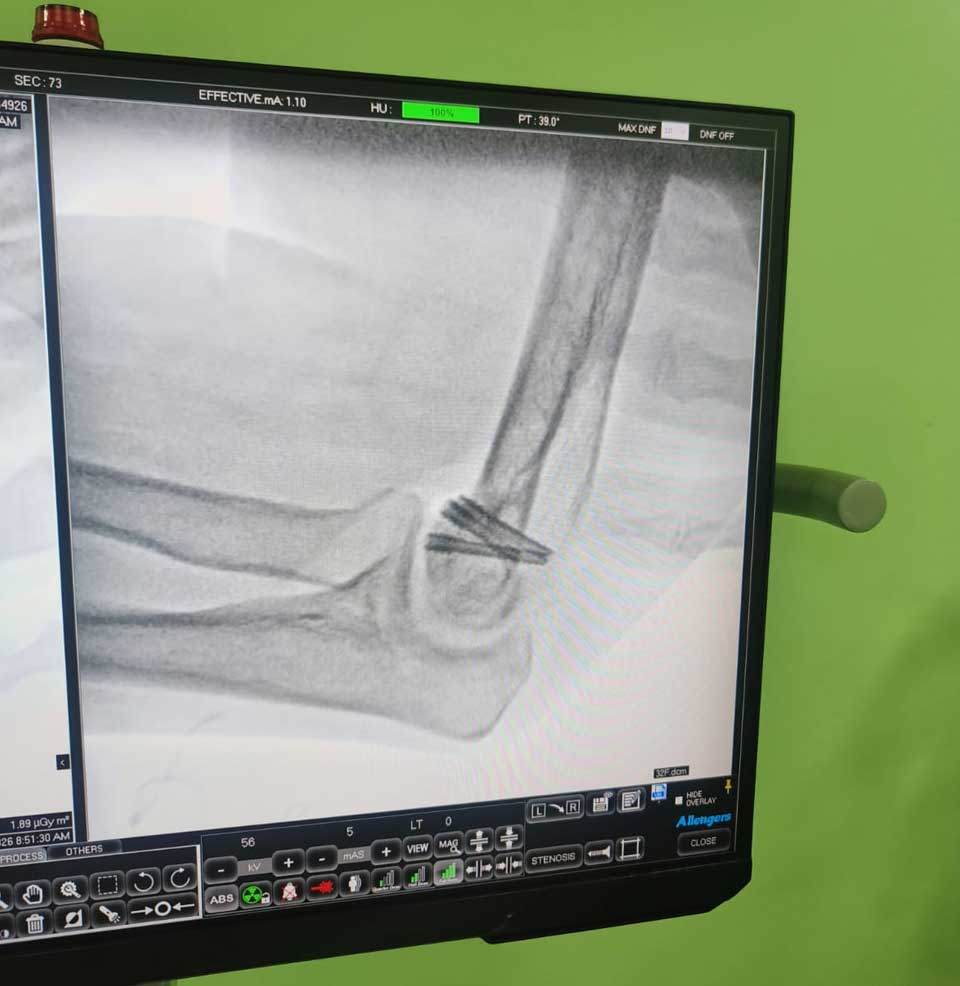

Our Image Gallery